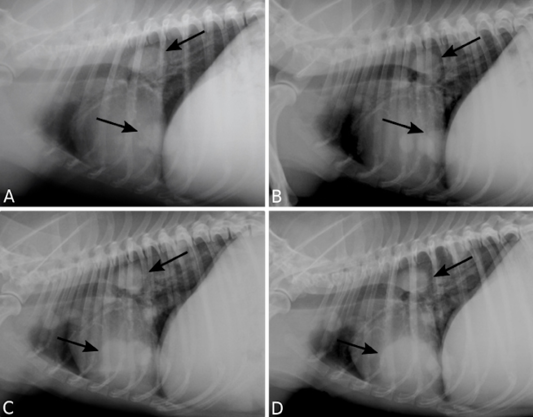

Pulmonary metastasis of a canine mammary gland carcinosarcoma. Right lateral recumbency thoracic radiographs (TR) presenting multiple nodules (arrows). TR performed 12 (A), 18 (B), 24 (C), 30 (D) months following surgical excision of the primary neoplasm.